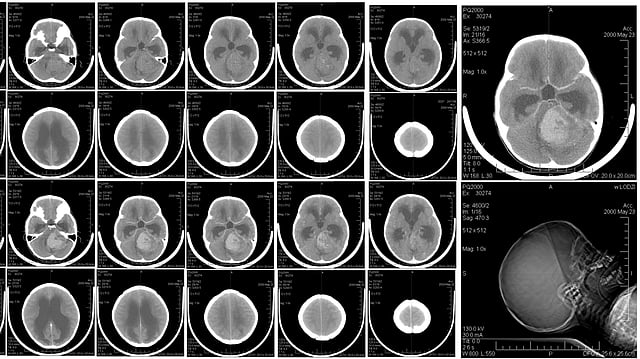

Medulloblastomas are one of the most common childhood brain cancers. Wikimedia Commons

Medulloblastomas are one of the most common childhood brain cancers.